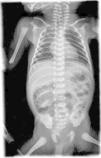

Se trata de un paciente varón de 5 meses de vida que ingresó en nuestro hospital por presentar vómitos proyectivos en la mitad y al final de las tomas, acompañados de una pérdida de peso de 350g en el transcurso de una semana. Como antecedentes destacaba que era un exprematuro moderado de 30 semanas de gestación que al quinto día de vida desarrolló una EN con neumatosis gástrica e intestinal (fig. 1), por lo que precisó una resección de 10cm del yeyuno y 25cm del íleon. Tras la intervención quirúrgica presentó varios episodios de retención gástrica y vómitos, con resolución espontánea y adecuada tolerancia posterior, por lo que se le dio el alta a su domicilio. Al reingreso presentaba un regular estado general, desnutrición grave y palidez mucocutánea, sin signos de deshidratación ni edemas periféricos. El peso, la talla y el perímetro cefálico estaban por debajo del percentil 3 para la edad corregida. A la palpación abdominal se apreciaba un ruido de vaciamiento gástrico rápido. Dada la imposibilidad de alimentación por vía oral se inició nutrición enteral a débito continuo por sonda nasogástrica, que fue bien tolerada. Se realizó un tránsito esofagogastroduodenal en el que se apreció una gastroparesia con retención de la papilla de bario en el estómago a las 6h. La ecografía abdominal no mostró alteraciones. En la endoscopia digestiva superior se visualizó un cuerpo gástrico distorsionado, sin solución de continuidad hacia el antro. Como única salida hacia el duodeno había un orificio de 2mm que no permitía el paso del endoscopio. Se realizó una laparotomía exploradora en la que se encontró una lesión fibrosa e indurada en la curvatura mayor del estómago, que se resecó y se realizó una anastomosis término-terminal. La evolución posterior fue satisfactoria y presentó una correcta transición de la nutrición por sonda nasogástrica a la vía oral y una buena ganancia pondoestatural.